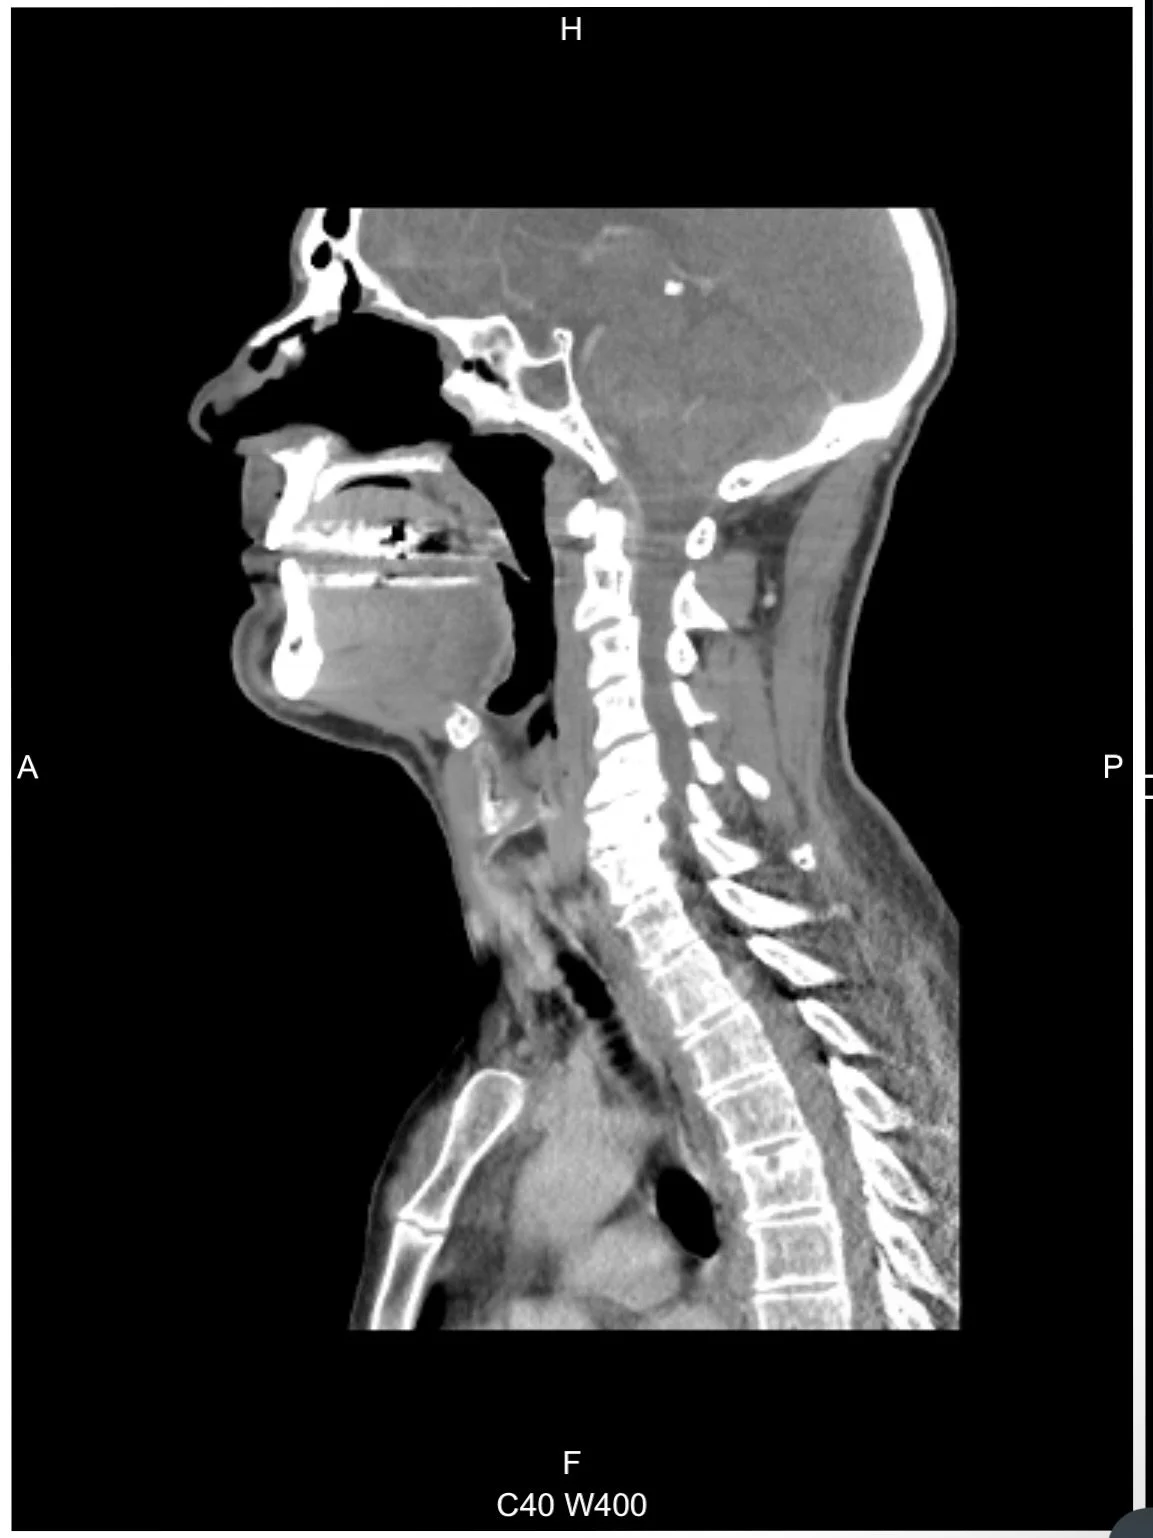

Soon afterward, a follow-up MRI revealed abnormal lumps in two lymph nodes in my neck, one of which tested positive for metastatic cancer. This marked my third battle with the disease since 2016 and became a significant breaking point in my life.